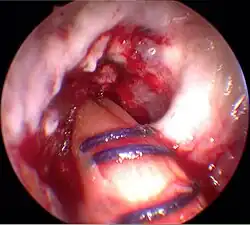

Einziehen des Transplantates

Mit zwei Zugfäden wird das Transplantat von unten nach oben in die Bohrkanäle eingezogen. Mit Hilfe einer Hohlschraube (Transfix-Schraube) wird das Transplantat am Oberschenkelknochen befestigt. Das aus dem Ende des Schienbeinkanals herausragende Ende wird vorgespannt und mit einer Interferenzschraube (Delta-Schraube) durch Verklemmung fixiert. Abschließend werden die Wunden vernäht. Die Operationsdauer liegt typischerweise im Bereich von 45 bis 90 Minuten.